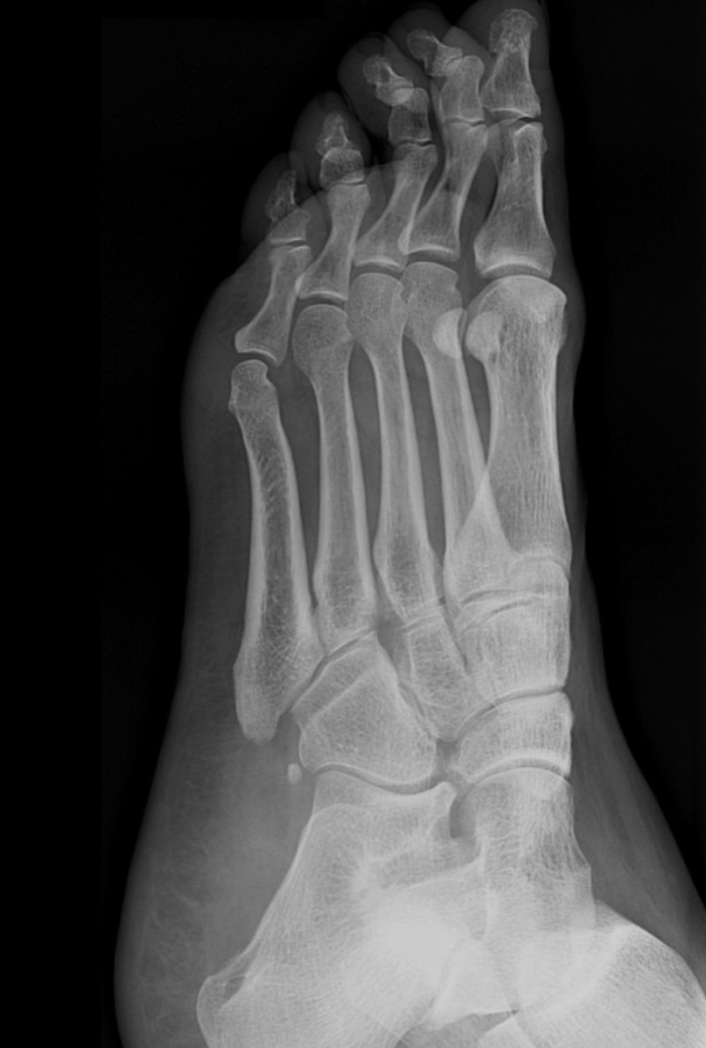

Q

What view is this?

A

Medial Oblique